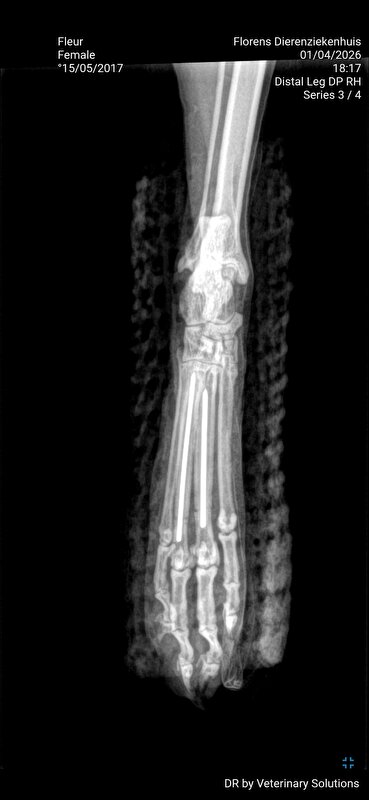

Dag 2: ik laat Fleur achter voor het maken van de foto's. Aan de assistente vertel ik dat Fleur zich goed gedraagt. Fleur is nml best een lief poesje. Er worden 3 foto's gemaakt en deze hoop ik nog te ontvangen om hier te kunnen plaatsen. 2 teentjes gebroken en 1 bot dusdanig naar buiten gekanteld dat deze bijna door steekt.